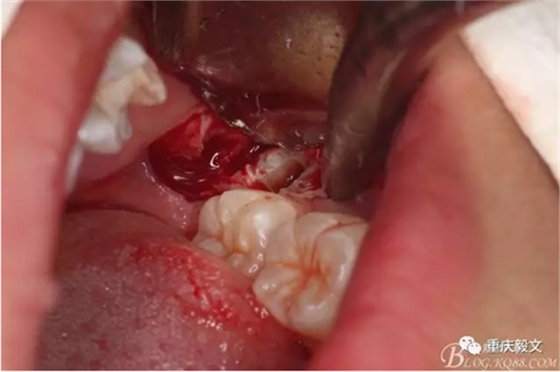

圖5切開(kāi)、翻瓣、去骨、暴露38牙冠。翻瓣從兩個(gè)切口的交接處開(kāi)始。掀起的瓣是全厚瓣。